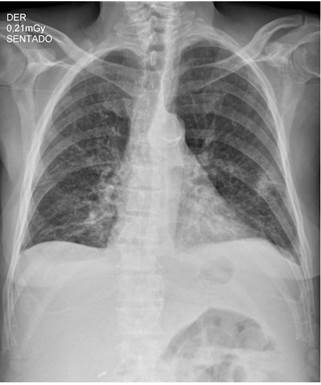

Ingresó por un cuadro clínico de 9 meses de evolución consistente en pérdida de peso de aproximadamente 12 kg, sudoración nocturna, astenia, adinamia y tos ocasionalmente productiva en el último mes. Adicionalmente, manifestó tener deposiciones diarreicas sin moco ni sangre, aproximadamente de 4 a 5 deposiciones al día durante 4 días antes del ingreso, la cual resolvió por sí mismo con hidratación y medidas generales. Al ingreso se documentó fiebre en 38,3 °C, palidez generalizada y taquicardia; y los exámenes de laboratorio iniciales documentaron leucopenia, anemia de volúmenes bajos en criterios de transfusión, trombocitopenia, hiponatremia leve hipovolémica hipoosmolar, hipomagnesemia e hipoalbuminemia (Figura 1 y Tabla 1). En el estudio de tomografía de tórax se obtuvieron hallazgos compatibles con silicoantracosis e imágenes hipodensas en las vértebras de carácter inespecífico (Figura 2).